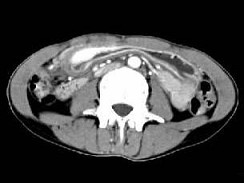

根据所提供的图像,最可能的诊断为()

• A.胃淋巴瘤

• B.胃癌

• C.胃炎性病变

• D.胃平滑肌瘤

• E.间质瘤